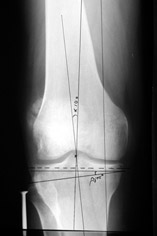

Уважаемые коллеги, много работ посвящено коррекции деформаций конечностей (варусной, вальгусной, торсионной), НЕ ВАЖЕН способ фиксации, важен подход – правильная биомеханическая коррекция, что достигается правильным определением уровня деформации (бедро, голень) и соответственно, правильным определением уровня коррекции.

Аппаратная коррекция очень грамотно изложена в диссертации Белокрылова Николая Михайловича «Хирургическая тактика лечения деформирующего гонартроза» Пермь 1998г. В моей работе описаны методы коррекции с накостным остеосинтезом. «Корригирующие операции в лечении гонартроза» Москва 2003г.